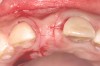

Fig 1. Case 1: A horizontal releasing incision across the edentate ridge at the site of tooth No. 8. It terminates 1 mm from the adjacent teeth.

Figure 1